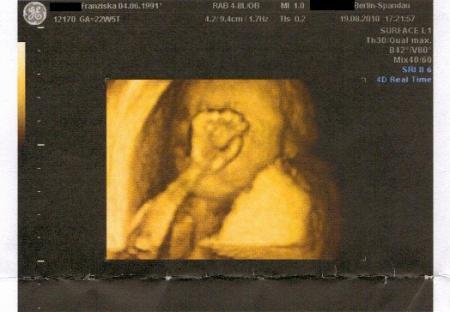

Sooo. Nun hatte auch ich gestern meine Feindiagnostik :D Es war soo schön das alles zu sehen Und es ist alles bestens! Es ist alles dort wo es sein muss, es ist alles so groß wie es sein muss, und es tut alles das was es tun muss ;D Baby wiegt jetzt so 514 gr. Oh man ich schlepp nen halbes Kilo Baby mit mir rum. Schon irgendwie komisch Und es hat sich diesmal auch nochmal bestätigt das es ein Mädchen wird, das wär ja was gewesen wenn da aufeinmal ein Pipimann gewesen wäre lach. Hat sich anfangs erstmal hinter ihrer Hand versteckt, zwischendurch hat sie dann doch ihr Gesicht gezeigt und mein FA hat ein schönes Bild davon machen können Er hat mich auch nach Hebamme und Krankenhaus gefragt, ob ich schon welche in aussicht hab und fragte ob ich dort entbinde wo meine Schwester entbunden hat (was der sich so alles merkt, wo meine Schwester vor 4 Jahren entbunden hat lach) und hat mir dann noch ein Heft mitgegeben mit allen Kliniken in Berlin und was die anbieten etc. :) Ich glaube der hatte aber bisschn schlechte laune, war scheinbar viel los an dem Tag. (waren insgesamt fast 2 Stunden dort wovon ca. 1 Stunde Wartezeit war) Aber er hat sich bemüht sich nichts anmerken zu lassen ;D Ist ja auch schon ein alter Mann, der darf ruhig mal erschöpft sein am Abend Und mein Verlobter ist ganz begeistert! Heute früh als er los ist zur Arbeit hatte er total gute Laune, auf meine Frage hin wieso er so gut gelaunt ist meinte er: "Ich bin einfach glücklich das es unserem Baby gut geht!" Hach, wie süß! Und ab dem 14.10. muss ich schon alle 2 Wochen hin. Wie die Zeit vergeht Und nun zu meiner Frage: Ich bin der Meinung hier gelesen zu haben das man aus den Daten die Länge des Babys ausrechnen kann? Kann mir bitte jemand sagen wie??? Achja. Aktuelles Gewicht: 60,4 kg Hab mich schon gefürchtet vor der Zahl auf der Waage Aber es hat ja wenigstens einen guten Grund :) Mein aktueller Spitzname bei meinem Verlobten: Kugelbauch Und Babys Spitzname: mutierter Erdnussflip. Und morgen in einer Woche bin ich schon im 7. Monat Wünsche euch einen schönen Start ins Wochenende, hoffen wir das es gutes Wetter gibt! GLG, Franzi (die überglücklich ist ) P.S.: Profil-US von der Kleinen :)

Bild zu Gestern FD + Frage - Forum für Dezember - Mamis